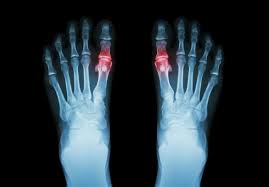

통풍은 요산이 과다로 생성되거나 요산의 배출에 장애가 발생할 경우 통풍 증상이 나타나게 됩니다.

요산이란 우리가 먹는 음식이 소화되어 최종적으로 대사하고 난 후 나오는 물질입니다. 보통 혈액 내에 녹아 있다가 소변으로 배출됩니다. 통풍 환자는 혈액 내 요산이 지나치게 많습니다. 이처럼 과다 축적된 요산은 결정체로 변하고, 이 요산 결정체가 관절 내에 침착하여 염증을 유발합니다.

통풍은 요산을 생성하는 퓨린이 다량 함유된 음식을 장기간 섭취하거나 술과 기름진 음식을 많이 섭취하여 몸 안에 요산이 축적될 경우 서구화된 식습관과 운동부족 스트레스 과다 체중 증가 등으로 인해 요산이 과다 생성되며 이들이 체외로 배출되지 못하고 관절과 힘줄 등에 쌓여 극심한 통증을 유발하게 됩니다.